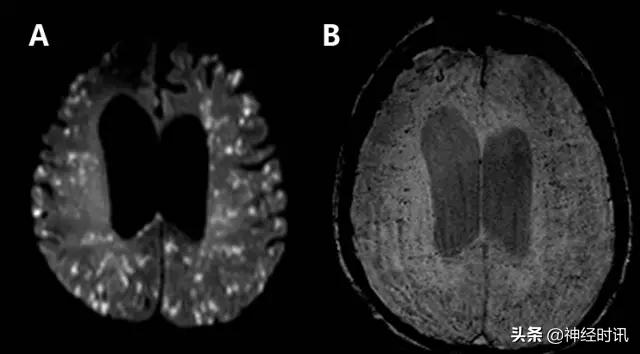

MELAS(线粒体脑病伴乳酸性酸中毒卒中样发作)

MELAS表现为恶心、呕吐、癫痫发作、肌无力和急性神经功能缺损,通常在40岁以前发病。MRI显示皮质和皮层下白质T2高信号、水肿和弥散受限。鉴别因素包括疾病进展不同阶段的多发病灶,急性病灶内同时存在弥散受限和增加,非血管性分布,以及好发于后部顶叶和枕叶(图6)。

图6 一例48岁男性,近期2次左侧PCA分布区梗死,伴神经功能缺损加重,新发认知功能障碍和意识障碍。最终诊断为MELAS,FLAIR显示左侧后顶颞针叶非血管性分布的皮层水肿(A:FLAIR),同时伴弥散受限和弥散增加(B:DWI;C:ADC)。